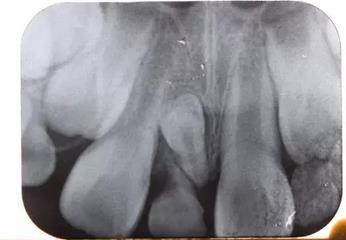

X線片:51牙根基本吸收,下方顯示倒置多生牙。